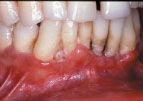

It is well known in the dental community that the emergence of the HIV infection in the early 1980s was accompanied by an explosion of some common and some rarer oral conditions including candida infections, Kaposi’s sarcoma, hairy leukoplakia, and a variety of other bacterial infections. In addition, HIV-associated infections associated with the periodontium included a linear gingival erythema (Fig. 3), necrotizing gingivitis (Fig. 4), human papilloma virus, and most seriously a necrotizing periodontitis with both soft- and hard-tissue necrosis that could extend beyond the periodontal tissues (Figs. 5-7).